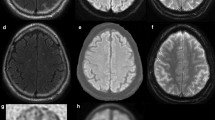

Chio A, Pagani M, Agosta F, Calvo A, Cistaro A, Filippi M. Neuroimaging in amyotrophic lateral sclerosis: insights into structural and functional changes. Lancet Neurol. 2014;13(12):1228–40. doi:10.1016/S1474-4422(14)70167-X.

Peretti-Viton P, Azulay JP, Trefouret S, Brunel H, Daniel C, Viton JM, et al. MRI of the intracranial corticospinal tracts in amyotrophic and primary lateral sclerosis. Neuroradiology. 1999;41(10):744–9.

Waragai M. MRI and clinical features in amyotrophic lateral sclerosis. Neuroradiology. 1997;39(12):847–51.

Cardenas-Blanco A, Machts J, Acosta-Cabronero J, Kaufmann J, Abdulla S, Kollewe K, et al. Structural and diffusion imaging versus clinical assessment to monitor amyotrophic lateral sclerosis. Neuroimage Clin. 2016;11:408–14. doi:10.1016/j.nicl.2016.03.011.

Sheng L, Ma H, Zhong J, Shang H, Shi H, Pan P. Motor and extra-motor gray matter atrophy in amyotrophic lateral sclerosis: quantitative meta-analyses of voxel-based morphometry studies. Neurobiol Aging. 2015;36(12):3288–99. doi:10.1016/j.neurobiolaging.2015.08.018.

Filippini N, Douaud G, Mackay CE, Knight S, Talbot K, Turner MR. Corpus callosum involvement is a consistent feature of amyotrophic lateral sclerosis. Neurology. 2010;75(18):1645–52. doi:10.1212/WNL.0b013e3181fb84d1.